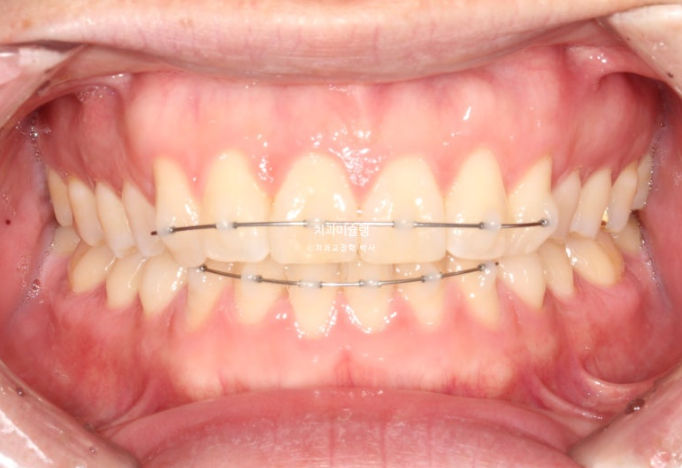

25.04

중심선이 맞지 않고 잇몸라인이 들쑥날쑥 합니다.

잇몸라인이 들쑥날쑥한 이유는 덧니 때문입니다.

어금니 교합관계는 좌우가 다른 상태라 위아래 중심선이 맞지 않습니다.

이렇게 측절치만 튀어나가있고 중절치는 옥니처럼 안으로 들어간 상태를 2급 2류 부정교합이라고 합니다.

MTA 장치와 설측 2D 장치중 보이는 것 상관없다 하여 MTA 추천드렸습니다.